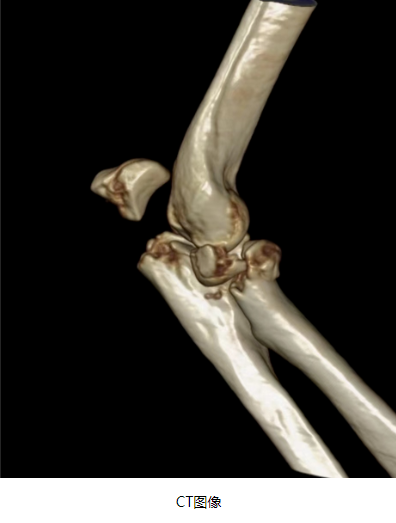

右侧尺骨鹰嘴骨折

桡骨头也骨折了

右侧桡骨头置换术+右侧尺骨鹰嘴骨折切开复位内固定术